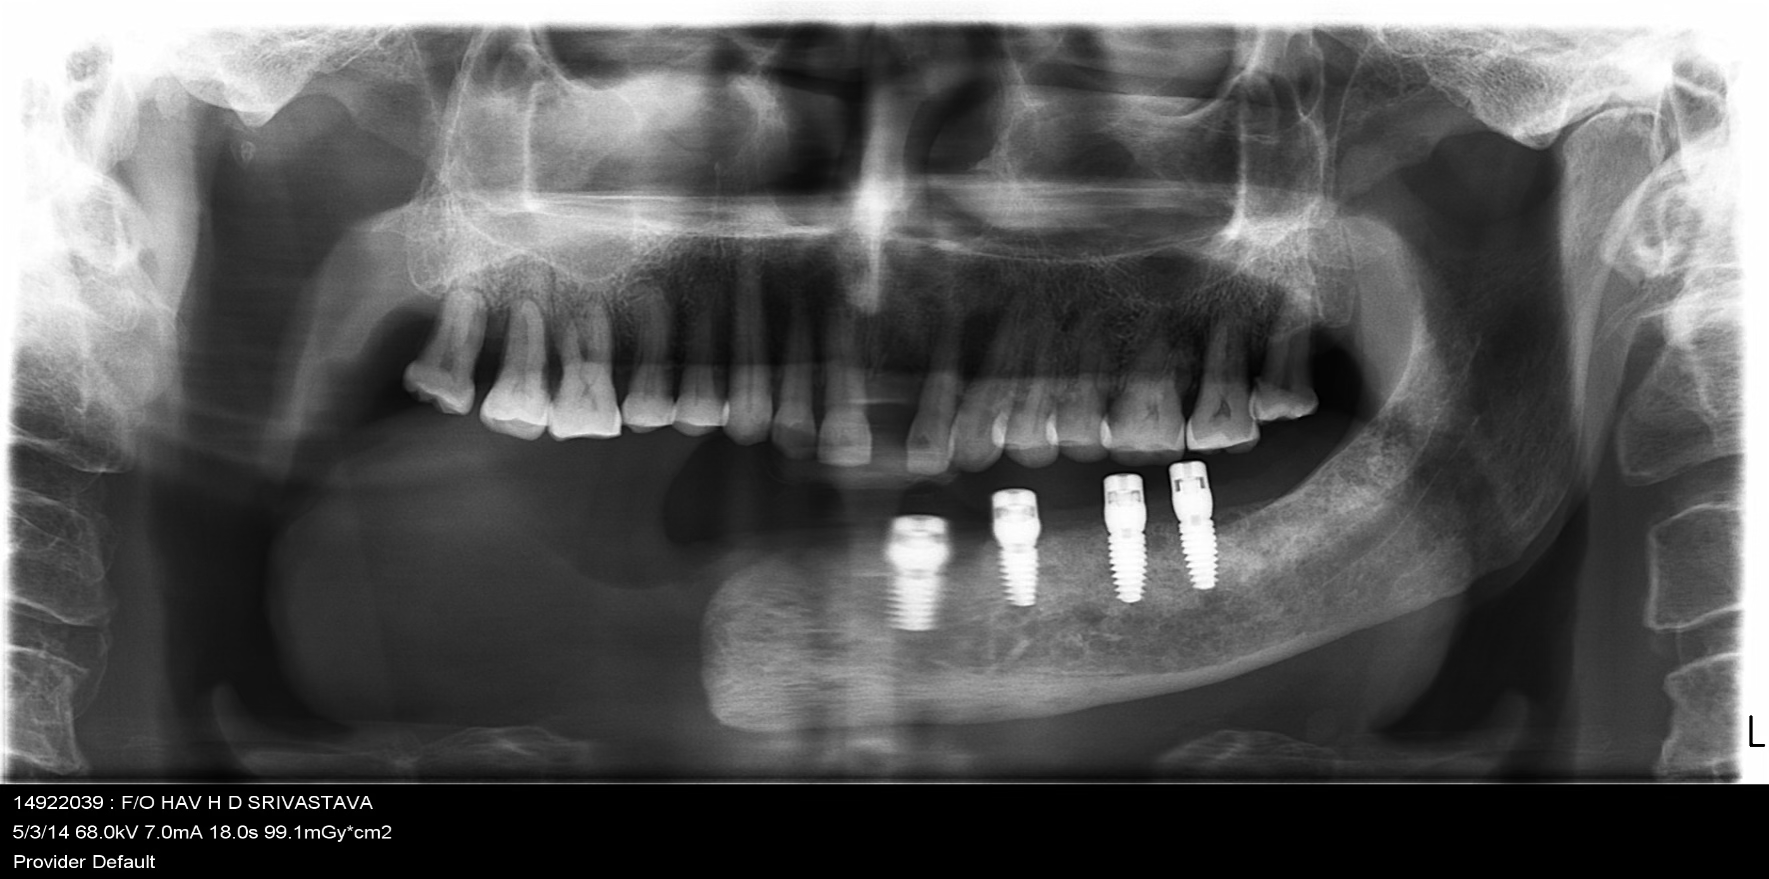

Comprehensive evaluation of oral cancer survivor post-hemimandibulectomy. Patient presented with missing teeth 16, 17, 25, 26, 31-37 and excised right mandible. Complete assessment of remaining bone and soft tissue.

Strategic placement of 4 Dio dental implants in the regions 32, 33, 35, and 36 using advanced surgical techniques suitable for post-cancer reconstructed anatomy.

Implants were delayed loaded after 3 months with PFM crowns. Precision-attached metal removable denture was inserted for comprehensive hemimandibulectomy rehabilitation.